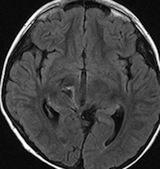

放射線治療後7週目

フレア画像です。腫瘍サイズが増大しています。もともと腫瘍周辺浮腫はなかったのですが大脳基底核と視床に浮腫が出現しています。スード・プログレッションの始まりです。

放射線治療後9週目

フレア画像です。たった2週間で脳浮腫が高度の脳浮腫となっています。失語症と右片麻痺と認知機能低下が生じました。ステロイド剤とグリセリンの点滴を行いました。